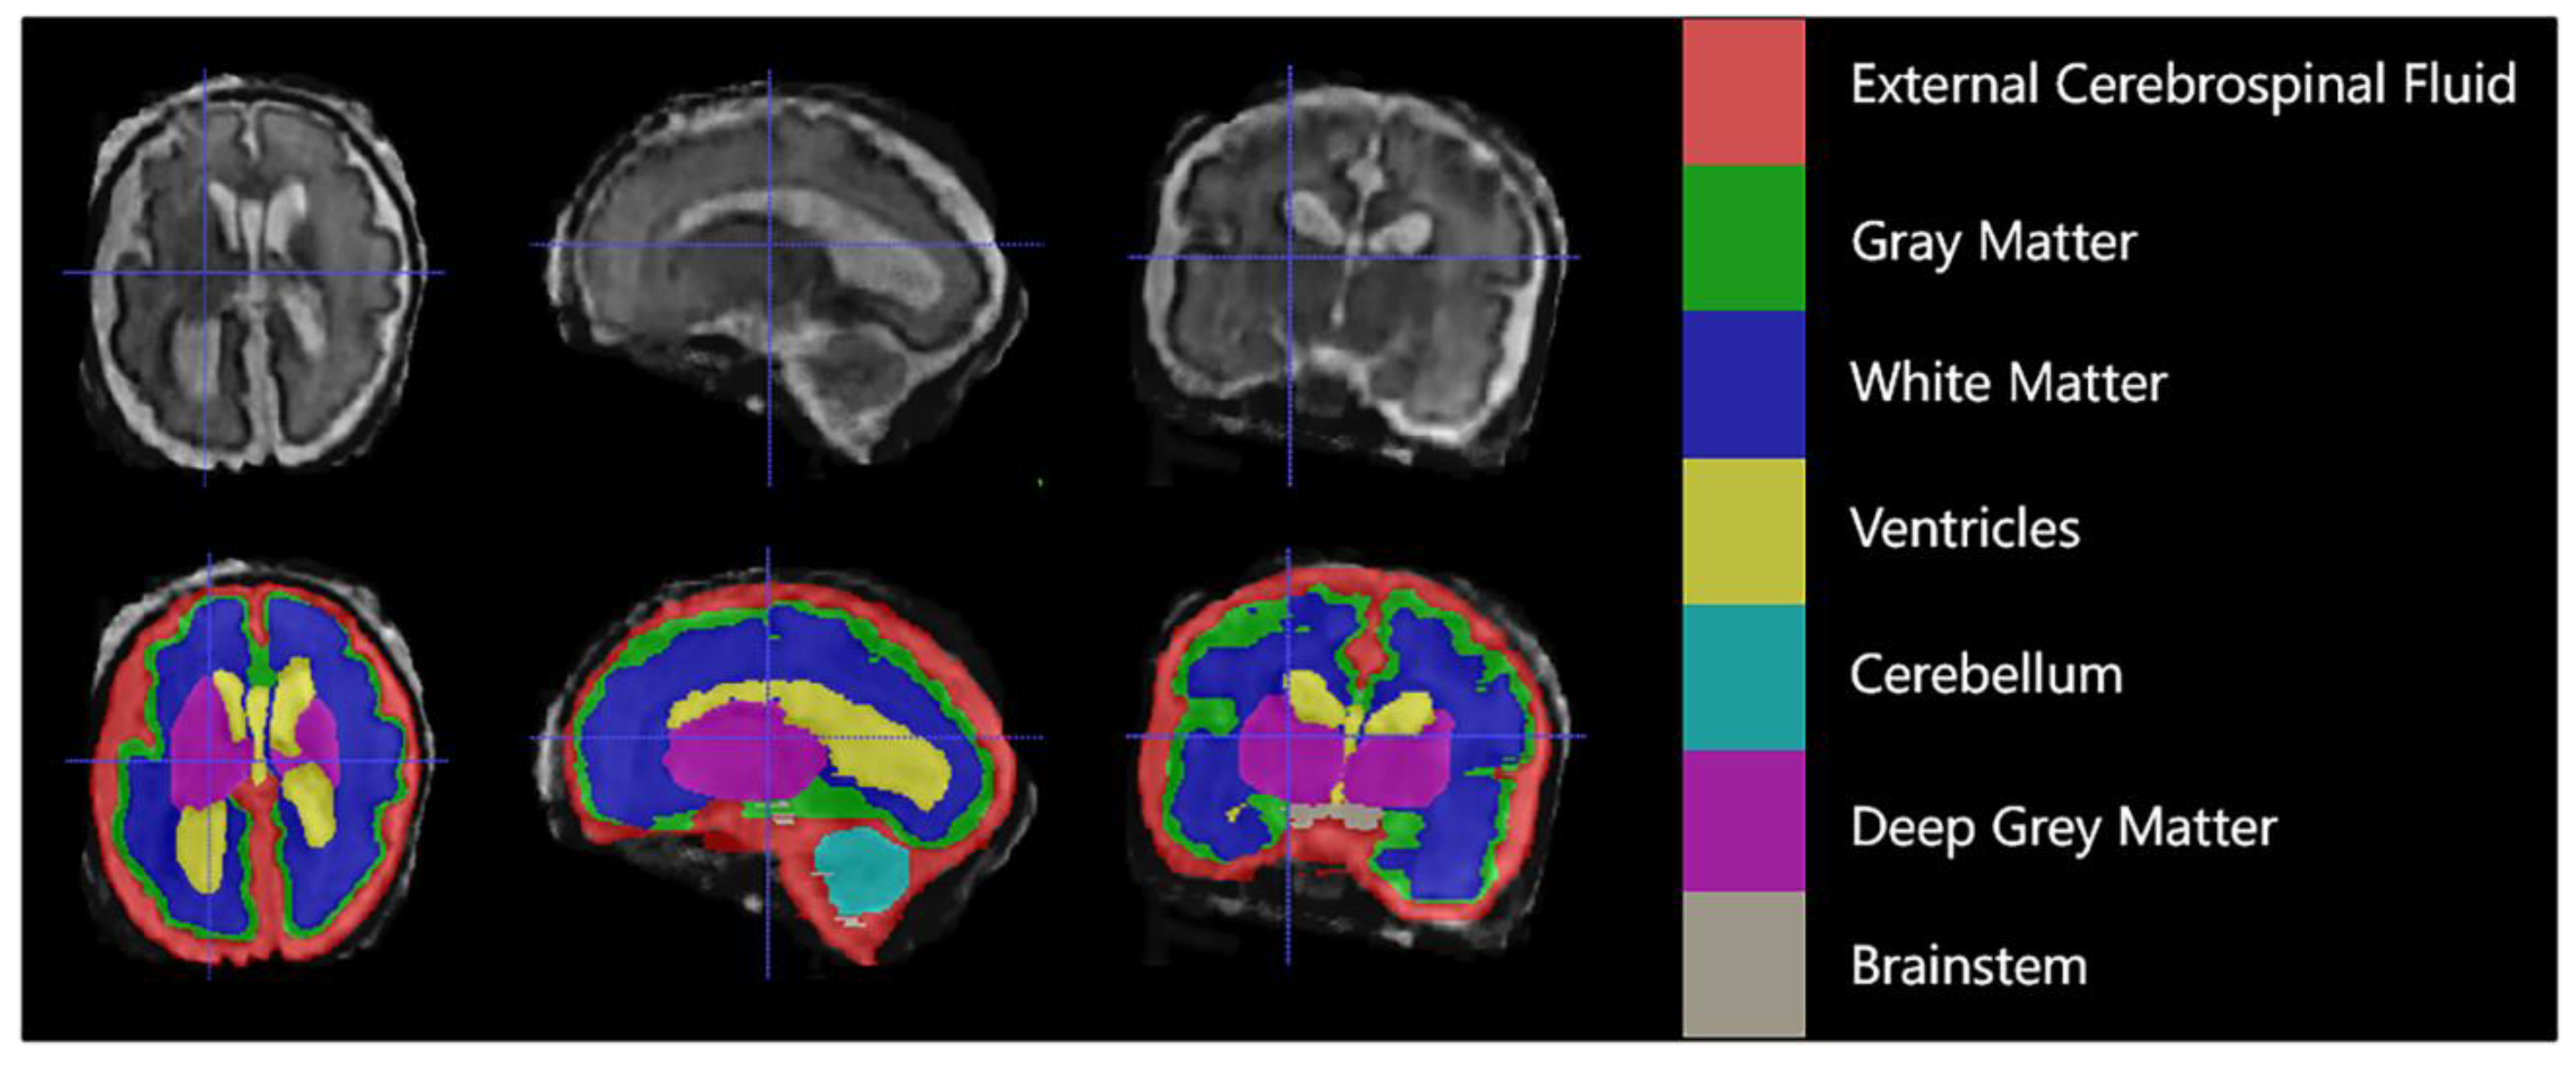

Each case consisted of a 3D superresolution reconstruction of the fetal brain (256 × 256 × 256 voxels). Training cases had an annotated label map corresponding to 7 different brain tissue types: external cerebrospinal fluid (eCSF), gray matter (GM), white matter (WM), lateral ventricles (LV), cerebellum (CB), deep gray matter (DGM), and brainstem (BS). As shown in Figure 1 below.

Figure 1.

An example of manual segmentation (red: external cerebrospinal fluid; green: GM; dark blue: WM; yellow: ventricles; cyan: cerebellum; maroon: deep GM: gray: brainstem).